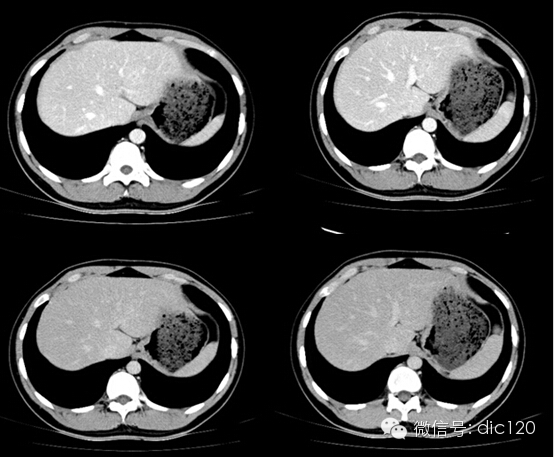

影像表現(xiàn):CT平掃與正常肝組織呈等密度,密度均勻,動(dòng)脈期病灶快速明顯均勻強(qiáng)化,中心見小片狀低密度影(瘢痕),門脈期及延遲期對比劑快速退出呈等密度,中央低密度影延遲強(qiáng)化。MRI腫塊T2WI為稍高信號(hào),中央高信號(hào)。動(dòng)態(tài)增強(qiáng)掃描動(dòng)脈期均顯著增強(qiáng),門脈期輕度增強(qiáng),延遲期瘢痕強(qiáng)化。

FNH具有離心性血液供應(yīng)及二條血液引流途徑。FNH的典型CT表現(xiàn)包括增強(qiáng)早期腫瘤呈彌漫均勻強(qiáng)化,在門靜脈期或門靜脈后期成等密度,病灶內(nèi)可見中心低密度瘢痕及輻射狀分隔,腫瘤周圍有薄而不完整的包膜樣血管。瘢痕是FNH 另一個(gè)重要影像學(xué)表現(xiàn),尤其是延遲掃描瘢痕強(qiáng)化為其特征。